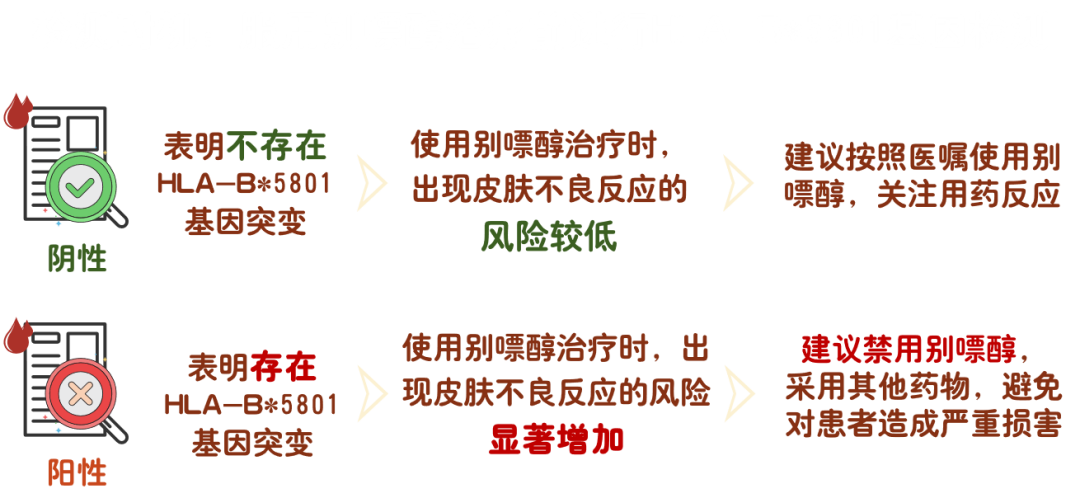

研究发现 :

HLA-B*5801 基因与亚裔人群服用别嘌醇引起的严重皮肤不良反应显著相关。服用别嘌醇后出现严重不良反应的患者中HLA-B*5801 基因携带率为 100%[3],且中国人群HLA-B*5801 基因频率比其他地区人群频率更高,可达 8%-20%[4]。研究显示,在服用别嘌醇前进行 HLA-B*5801 基因检测可显著降低别嘌醇引起的严重皮肤不良反应的发生率。